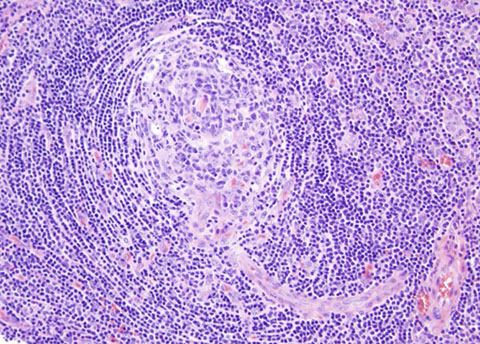

Reactive Follicular Hyperplasia (RFH). Follicles (B-cell compartment) have varying size and are well spaced from one another. There is a nice capsule and subcapsular sinus. In medullary compartment where plasma cells and memory B-cell live, the sinuses are open and patent. Note the relative abundance of the paracortex compared to the cortex, which is an important feature for B9 LNs.

Hyperplastic lymphoid follicle. Germinal center with sharply demarcated mantle zone (solid blue arrow). Dark zone of GC with starry-sky pattern (open blue arrow) and light zone (open black arrow) with small centrocyte predominance [2]

High magnification of GC with centroblasts (solid blue line) mixed with histiocytes with clear cytoplasm with nuclear fragments (open black line) and frequent mitoses (curved black line)